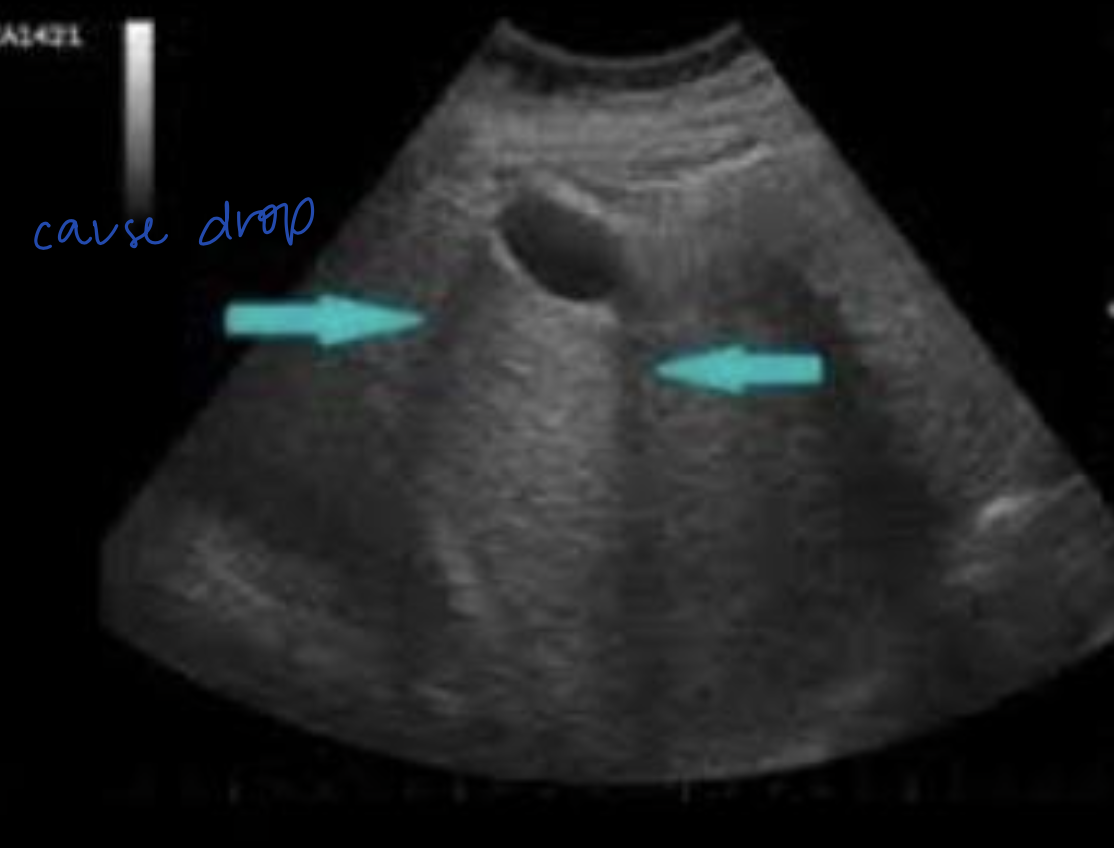

What ultrasound artifact causes (artificial) brightness DEEP to an anechoic structure?

Acoustic Enhancement